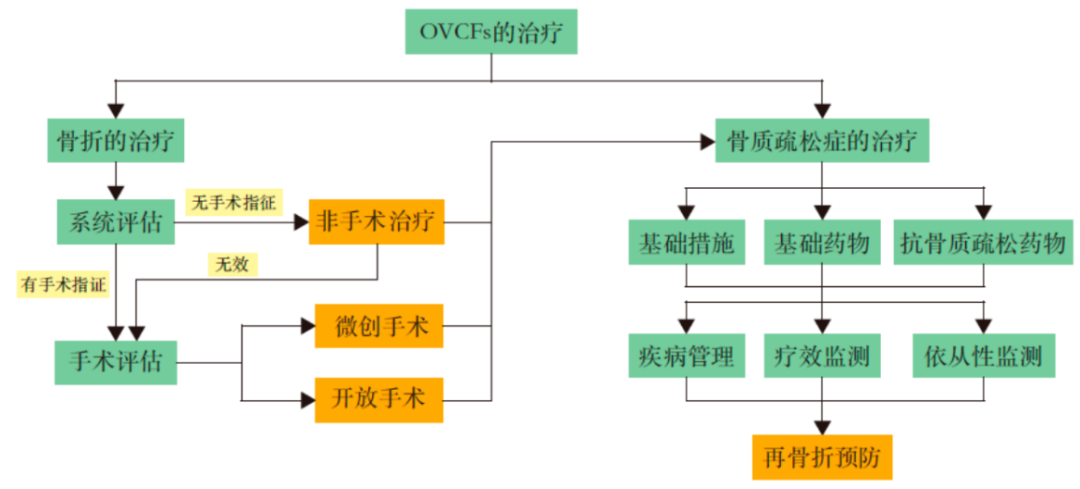

复位、固定、功能锻炼和抗骨质疏松是骨质疏松性骨折的基本治疗原则,同样适用于OVCFs。稳定骨折椎体,缓解疼痛,加强功能锻炼,并进行规范的抗骨质疏松治疗,预防再骨折,方能取得良好疗效。

(1.)非手术治疗

A.适应证:症状及体征较轻,影像学检查为轻度压缩骨折、无神经功能损害、无法耐受手术者可采取非手术治疗。

B.治疗方法:包括卧床休息,药物镇痛,佩戴支具,早期活动和功能锻炼等

(2.)手术治疗

微创手术治疗

椎体强化手术,包括椎体成形术(PVP)和经皮球囊扩张椎体后凸成形术(PKP),是目前最常用的微创手术治疗方法。通过经皮向骨折椎体注射骨水泥,能够迅速缓解疼痛,增强病椎的强度和刚度,防止椎体进一步塌陷和畸形,而且没有传统开放手术内固定带来的手术创伤以及远期可能出现的内固定失败。PKP还可通过球囊扩张使压缩骨折得到一定程度的复位,球囊取出后在椎体内形成的空腔有利于骨水泥低压力注入,有效降低骨水泥渗漏率。

PVP

PKP

适应症:适用于非手术治疗无效,疼痛剧烈:不稳定的椎体压缩性骨折;椎体骨折不愈合或椎体内部囊性变、椎体坏死;椎体血管瘤;不宜长时间卧床;能耐受手术者;可达到减轻疼痛、稳定脊椎和早期活动的目的;对高龄患者宜考虑早期手术,可有效缩短卧床时间,减少骨折并发症的发生。

绝对禁忌证:不能耐受手术者;无痛、陈旧的骨质疏松性椎体压缩性骨折;手术节段的局部感染及无法控制的全身感染;严重的凝血功能障碍者;对椎体成形器械或材料过敏者。

相对禁忌证:椎体严重压缩性骨折,椎管内有骨块;有出血倾向者;身体其他部位存在活动性感染者;与椎体压缩骨折无关的神经压迫引起的根性痛。

开放手术治疗

对有脊髓及神经压迫症状和体征、严重后凸畸形、需行截骨矫形以及不适合行微创手术的不稳定椎体骨折患者,可考虑行手术治疗。

OVCFs 的病理基础是骨质疏松,手术只针对局部病变,因此除了骨折治疗以外,应积极采取措施进行系统地抗骨质疏松治疗,目的是缓解疼痛,抑制急性骨丢失,增加骨量,改善骨质量,降低再骨折发生率。